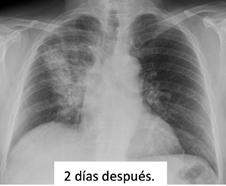

Durante las primeras horas de ingreso, se identificó FA con periodos autolimitados de bloqueo auriculoventricular completo, sin evidencia de hipoperfusión ni signos de insuficiencia cardiaca. La repetición del ecocardiograma trans-torácico no mostró progresión de la disección. A pesar de la compresión del hematoma cervical, la anemia progresó hasta 7,8 g/dL precisando transfusión de un concentrado de hematíes, y hubo agravamiento de la trombopenia precisando bolos de corticoides. Se pospuso la anticoagulación hasta cese de sangrado, reiniciándose bajo pauta de heparina no fraccionada, sin progresión adicional de la anemia. La paciente experimentó una evolución clínica favorable, con estabilidad hemodinámica, sin nuevos episodios de sangrado ni progresión de la disección aórtica. Precisó intervención quirúrgica en dos ocasiones, por pseudoaneurisma

y disección de la arteria radial derecha, respectivamente. Finalmente pudo ser dada de alta tras 22 días de ingreso (Figura 3), bajo anticoagulación con acenocumarol.

Dia 1: Implante de TAVI

Dia 3: Cese de sangrado. Reinicio de anticoagulación

Dia 2: Anemización. Transfusión de hematíes

Dias 8 y 9: Pseudoaneurisma radial derecho: Diagnóstico e intervención

Dias 16: Disección distal de arteria radial derecha: Diagnóstico e intervención Ingreso

Dia 2: Disección aórtica tipo A

Dia 2: Hematoma cervical derecho

Alta +22

Dia 7: Angio-TC de control

• Estabilidad de disección aórtica

• Reducción del hematoma cervical

Dia 2: Agudización de trombopenia

Administración de bolus de corticoides

Figuras 3: Timeline de eventos y complicaciones que tuvieron lugar desde el ingreso hasta el alta, en orden cronológico.